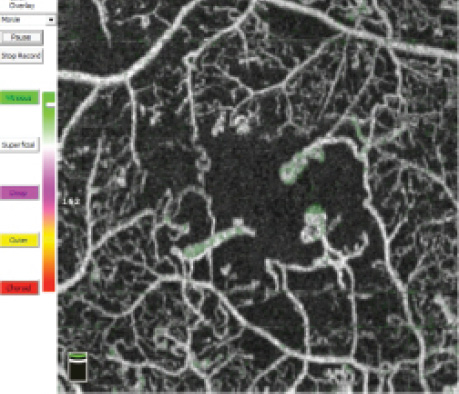

Video 1. Features of PDR

This video highlights features of PDR by segmenting the macula layer by layer.

In patients with DR, OCTA demonstrates retinal alterations including capillary dropout in the superficial and deep plexuses, FAZ enlargement, and microaneurysms (Figure 5). The ability to separately examine the superficial and deep capillary plexuses with OCTA helps users to delineate retinal involvement in various diabetic lesions (Video 1). For instance, widening of the FAZ is best seen in the superficial plexus, whereas capillary dropout and microaneurysms are best appreciated in the deep plexus. However, microaneurysms are visible on OCTA only in the presence of intravascular flow; therefore, those with slow flow or thrombosis will remain undetected. The detection of preretinal and prepapillary neovascularization is also facilitated with OCTA, as these new vessels are not blurred by leakage in dye-based angiography.